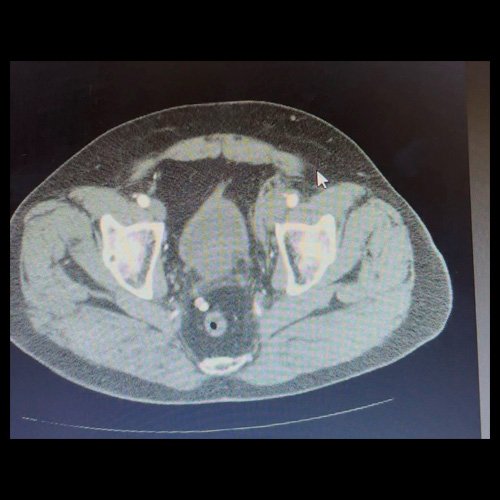

• AngioTAC de miembros inferiores (Día 2): Ateromatosis parietal calcificada parcheada en todo el territorio aorto-ilíaco-femoral bilateral. LADO DERECHO: Arteria ilíaca interna: de calibre y trayecto conservado, permeable. Arterias ilíaca externa y femoral común: de calibre y trayecto conservados, permeables. Arterias circunfleja ilíaca superficial y epigástrica superficial: de calibre y trayecto conservados, permeables. Arteria femoral superficial: de calibre y trayecto conservado, permeable. Arteria femoral profunda: de calibre y trayecto conservado, permeable. Arterias circunflejas femoral medial y lateral: de calibre y trayecto conservados, permeables. Arteria poplítea: de calibre y trayecto conservado, permeable. Arteria tibial anterior: de calibre y trayecto conservado, permeable. Arteria tibial posterior: de calibre y trayecto conservado, permeable. Vena ilíaca primitiva: 13 mm, vena ilíaca externa 11 mm, vena ilíaca interna 7 mm. LADO IZQUIERDO: En esta ocasión, en fase angiográfica se observa de calibre y opacificación conservada de las arterias femoral superficial y profunda, poplítea y de sus ramas musculares en muslo y pierna. En fase venosa se evidencia un defecto de relleno endoluminal de la vena primitiva izquierda que impresiona extenderse actualmente a la vena iliaca externa, a la vena femoral superficial y poplítea, hasta nivel del hueco homonimo, las cuales se visualizan aumentadas de calibre con respecto a sus contralaterales, en relación a trombosis venosa profunda. Se sugiere cotejar con ecodoppler de miembros inferiores. No se identifica compromiso de la porción visualizada de la vena cava inferior ni del sistema venoso ilíaco contralateral. Se visualiza dispositivo vascular en VCI (filtro VCI), infrayacente a las venas renales. Presenta aumento del diámetro del muslo izquierdo con respecto a su contralateral, asociado a edema de los tejidos blandos superficiales. Reticulación de la grasa de la región inguinal a predominio izquierdo con algunas burbujas aéreas. Se observa inmediatamente infrayacente a los antes mencionado, un área hiperdensa que realza en fase venosa, con centro hipodenso, que mide 2.2 cm x 1.4 cm, ya visualizado en tomografía previa. Cambios artrodegenerativos coxo-femorales y tricompartimentales en la rodilla. Signos de entesopatía cuadricipital distal. No se observan alteraciones a nivel del fémur ni de las porciones visualizadas de la tibia y el peroné. Arteria ilíaca interna: de calibre y trayecto conservado, permeable. Arterias ilíaca externa y femoral común: de calibre y trayecto conservados, permeables. Arterias circunfleja ilíaca superficial y epigástrica superficial: de calibre y trayecto conservados, permeables. Arteria femoral superficial: de calibre y trayecto conservado, permeable. Arteria femoral profunda: de calibre y trayecto conservado, permeable. Arterias circunflejas femoral medial y lateral: de calibre y trayecto conservados, permeables. Arteria poplítea, tibial anterior y tibial posterior: de calibre disminuido con respecto a su contralateral, permeables. Vena ilíaca primitiva: 14 mm, vena ilíaca externa 17 mm, vena ilíaca interna 9 mm. Calcificaciones en conducto inguinal bilateral. Hidrocele bilateral.

• TAC de abdomen y pelvis con contraste EV (Día 10): El hígado es de forma, tamaño y situación habituales. Su superficie es lisa, y sus bordes son agudos. No presenta alteraciones densitométricas ni efectos de masa focales. La vía biliar intra y extrahepática es de calibre conservado. La vesícula biliar es de forma, tamaño y situación normales, sin imágenes que sugieran la presencia de litiasis. Tener en cuenta que este método puede pasar por alto litiasis colesterínicas. El bazo es de forma, tamaño y situación normales. El eje esplenoportal es de calibre y trayecto conservado. El páncreas es de características normales. El conducto de Wirsung es de calibre conservado. Las glándulas adrenales son normales. Ambos riñones son de forma, tamaño y situación habituales. Sin evidencia de alteraciones calicopiélicas ni ureterales. Quistes simples corticales en riñón izquierdo, el mayor de ellos en polo superior, que mide 16 mm. Discreta reticulación de la grasa perirrenal bilateral. La aorta, las arterias ilíacas primitivas, internas, externas y femorales, son de calibre y trayecto conservado. La vena cava inferior y las venas ilíacas primitivas, internas, externas y femorales son de calibre y trayecto conservados. Filtro de vena cava inferior infrayacente a venas renales. No se observan adenomegalias intraperitoneales, retroperitoneales, ilíacas ni inguinales. No se observan alteraciones a nivel del tracto gastrointestinal. Abundante contenido de materia fecal en el colon. Vejiga con escasa repleción. La próstata y las vesículas seminales son de características normales. No se observa líquido libre ni neumoperitoneo Presenta aumento del diámetro de la raíz del muslo izquierdo con respecto a su contralateral, asociado a edema de los tejidos blandos superficiales. Reticulación de los tejidos blandos de la región inguinal izquierda, de mayor jerarquía que en estudio anterior, con tendencia a coleccionar. Además se observan ganglios locorregionales aumentados en número y tamaño sin alcanzar rango megálico. Se observa inmediatamente infrayacente a los antes mencionado, un área hiperdensa que realza en fase venosa, con centro hipodenso, que mide 2.2 cm x 1.4 cm, ya visualizado en tomografía previa, sin cambios. Calcificaciones en conducto inguinal bilateral. Hidrocele bilateral. Marcados cambios artrodegenerativos de la columna lumbosacra y coxo-femorales.

• Flebotomografia de miembros inferiores (Día 18): Filtro de vena cava inferior infrayacente a venas renales. Stent metálico a nivel de la vena ilíaca común y externa izquierda, permeable. Se explora la región venosa del territorio femoral y poplíteo, evidenciándose defectos parciales de relleno endoluminal a nivel de la vena femoral superficial y profunda izquierdas, compatibles con trombosis venosa parcial. A nivel del tercio distal de la vena femoral común izquierda, se evidencia aumento de calibre e interrupción brusca de la opacificación del contraste (“signo de stop”), compatible con trombosis venosa oclusiva en dicho nivel, sin opacificación venosa distal. Se observan similares hallazgos a nivel de la vena femoral superficial contralateral, evidenciándose defectos de relleno endoluminal parcial hasta su tercio distal, con ausencia de opacificación distal. Salvo mejor criterio sugiero complementar con eco-Doppler de venoso de ambos miembros inferiores. Presenta edema difuso de los tejidos blandos de miembro inferior izquierdo. Se observa en los tejidos blandos de la región inguinal izquierda, colección hipodensa con realce periférico que mide 4.7 cm AP x 4 cm. Además se observan ganglios locorregionales aumentados en número y tamaño, algunos de rango megálico.

TAC de tórax, abdomen y pelvis con contraste EV (Día 10) Corte axial